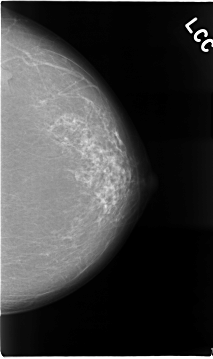

C_0016_1.LEFT_CC

LEFT_CC LINES 4664 PIXELS_PER_LINE 2768 BITS_PER_PIXEL 12 RESOLUTION 50 NON_OVERLAY